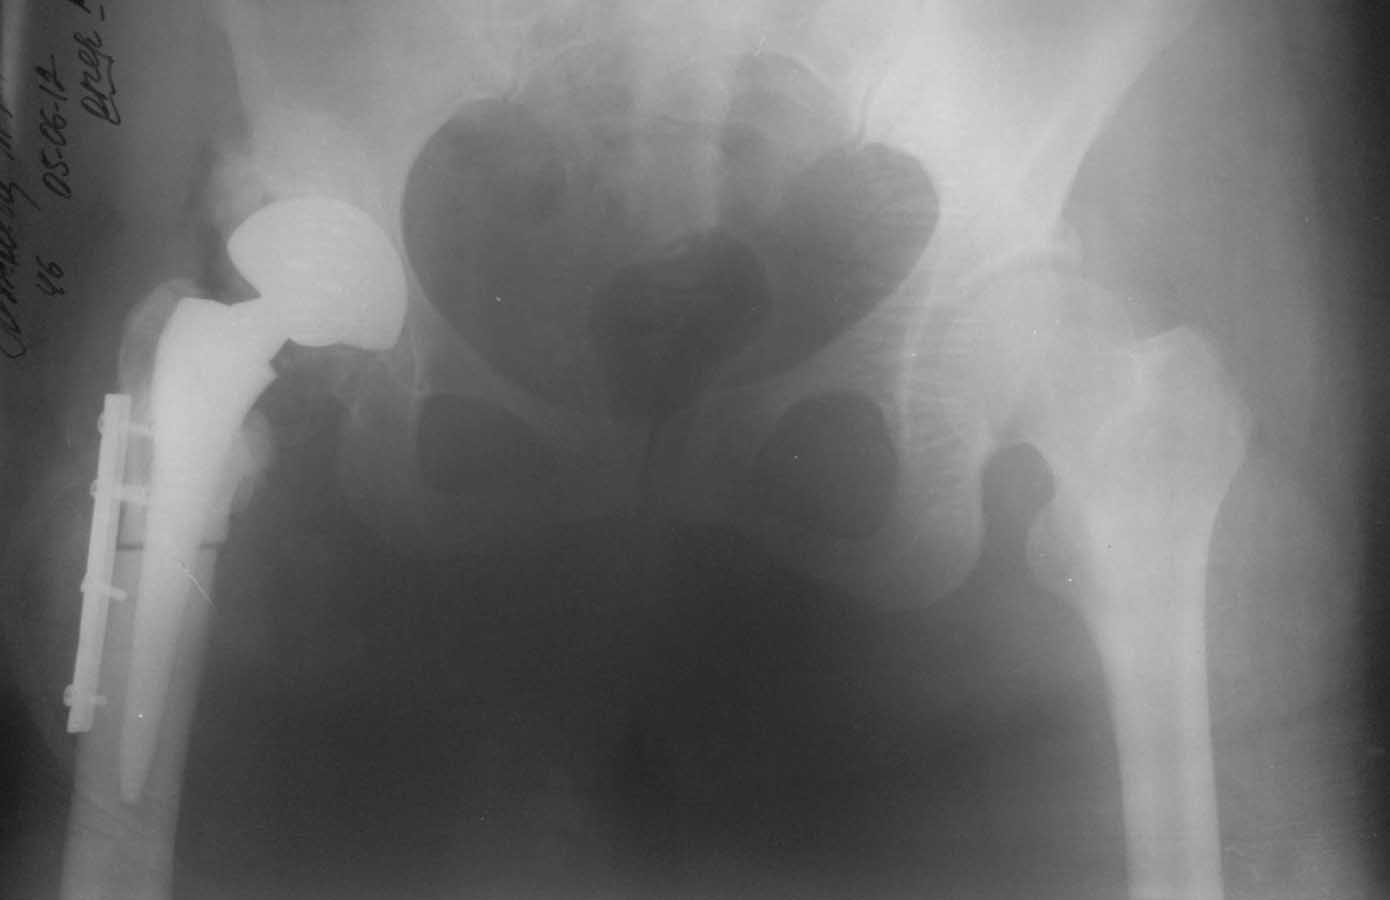

2. Бедренный компонент не выглядит стабильным, и стабильным на протезе с прокимальной фиксацией быть не может. Антиротационная пластинка слегка удерживает дистальный отломок, а плоскость остеотомии сложно назвать хорошо адаптированной. Из чего следует - бедренный компонент удалять. Вертлужный, если стабилен, можно оставить с заменой вкладыша

4. Костная импакционная пластика используется при значитальном дефиците костного ложа, которого здесь вроде не наблюдается. Поэтому если речь пойдет о спейсере, то я за цементный без пластики.

Не знаю как другие, но по выложенным рентгенограммах можно заподозрить лизис вдоль медиальной стенки дистального фрагмента. То что проксимальный фрагмент стабилен сомнений нет, по поводу дистального - как то сомнительно.

Конечно, гадать на таком рентгене - стабильны компоненты или нет - все равно что на кофейной гуще, можно сделать рентген в двух проекциях и без ротации ножки. Но точно определить можно лишь на ревизии. Будешь убирать или нет, спейсер или пластика или что-то еще(кто-то писал о вакуумном ведении протезной раны в течении недели после ревизии и дебридмента) - дело другое, но ревизовать надо. чем раньше тем лучше.

Фрагменты можно называть хорошо адаптироваными, но не менее хорошо видно диастаз между ними как минимум 3-4 мм на послеоперационном и последующем снимке.

Чуда не произошло... В суставе гной, все прикрепления ягодичных мышц, псоас, вастус латералис лизировались, сам ничего не убирал, при том, что с предыдущей операции уходили достаточно красиво, все было на месте. А сегодня - удручающая картина: голая мертвая кость до с/3 бедра, видимо сказались предыдущие операции.в связи с чем пришлось убрать проксимальный отдел бедра, установить спейсер. Явной нестабильности компонентов не было, впрочем убралось все легко, небольшие признаки остеоинтеграции на ножке и чашке. Пульс-лаваж- 5л с ловасептом. VAC наладить неудалось из-за множества грубых рубцов от предыдущих вмешательств (не герметично). Фото прилагаю.

Нельзя назвать абсолютно стабильной фиксацию дистального конца бедра, поскольку ножка слишком коротка. Вагнер был предпочтителен изначально. И антиротационный компонент там присутствует в виде ребер. Пластина, тем более такая короткая, пользы не приносит. Конечно и бактериальный компонент никто не отменял, но изначальная нестабильность сыграла пагубную роль.